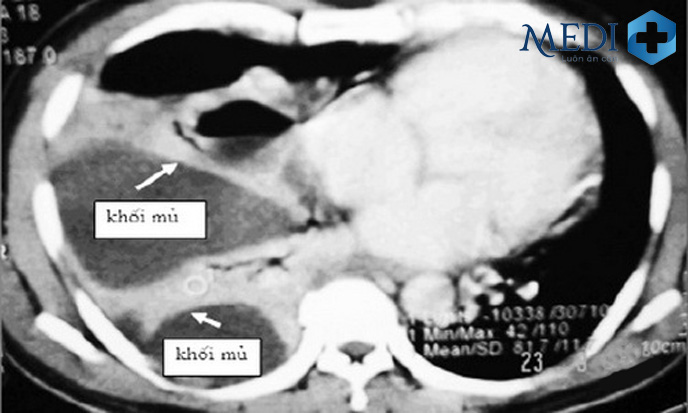

Viêm màng phổi mủ – Empyema

Empyema hay tràn mủ màng phổi là sự tăng tiết mủ bên trong khoang màng phổi gây khó khăn cho hoạt động giãn nở của phổi trong quá trình hít thở. Khi khoang màng phổi bị nhiễm trùng, nhiễm khuẩn thì hệ miễn dịch sẽ tăng cường hoạt động để chống lại sự tấn công của các tác nhân gây bệnh tạo nên những chất lỏng đậm đặc, đục màu bên trong khoang màng phổi.

Hình ảnh chụp X quang cho thấy các khối mủ trong phổi – Empyema